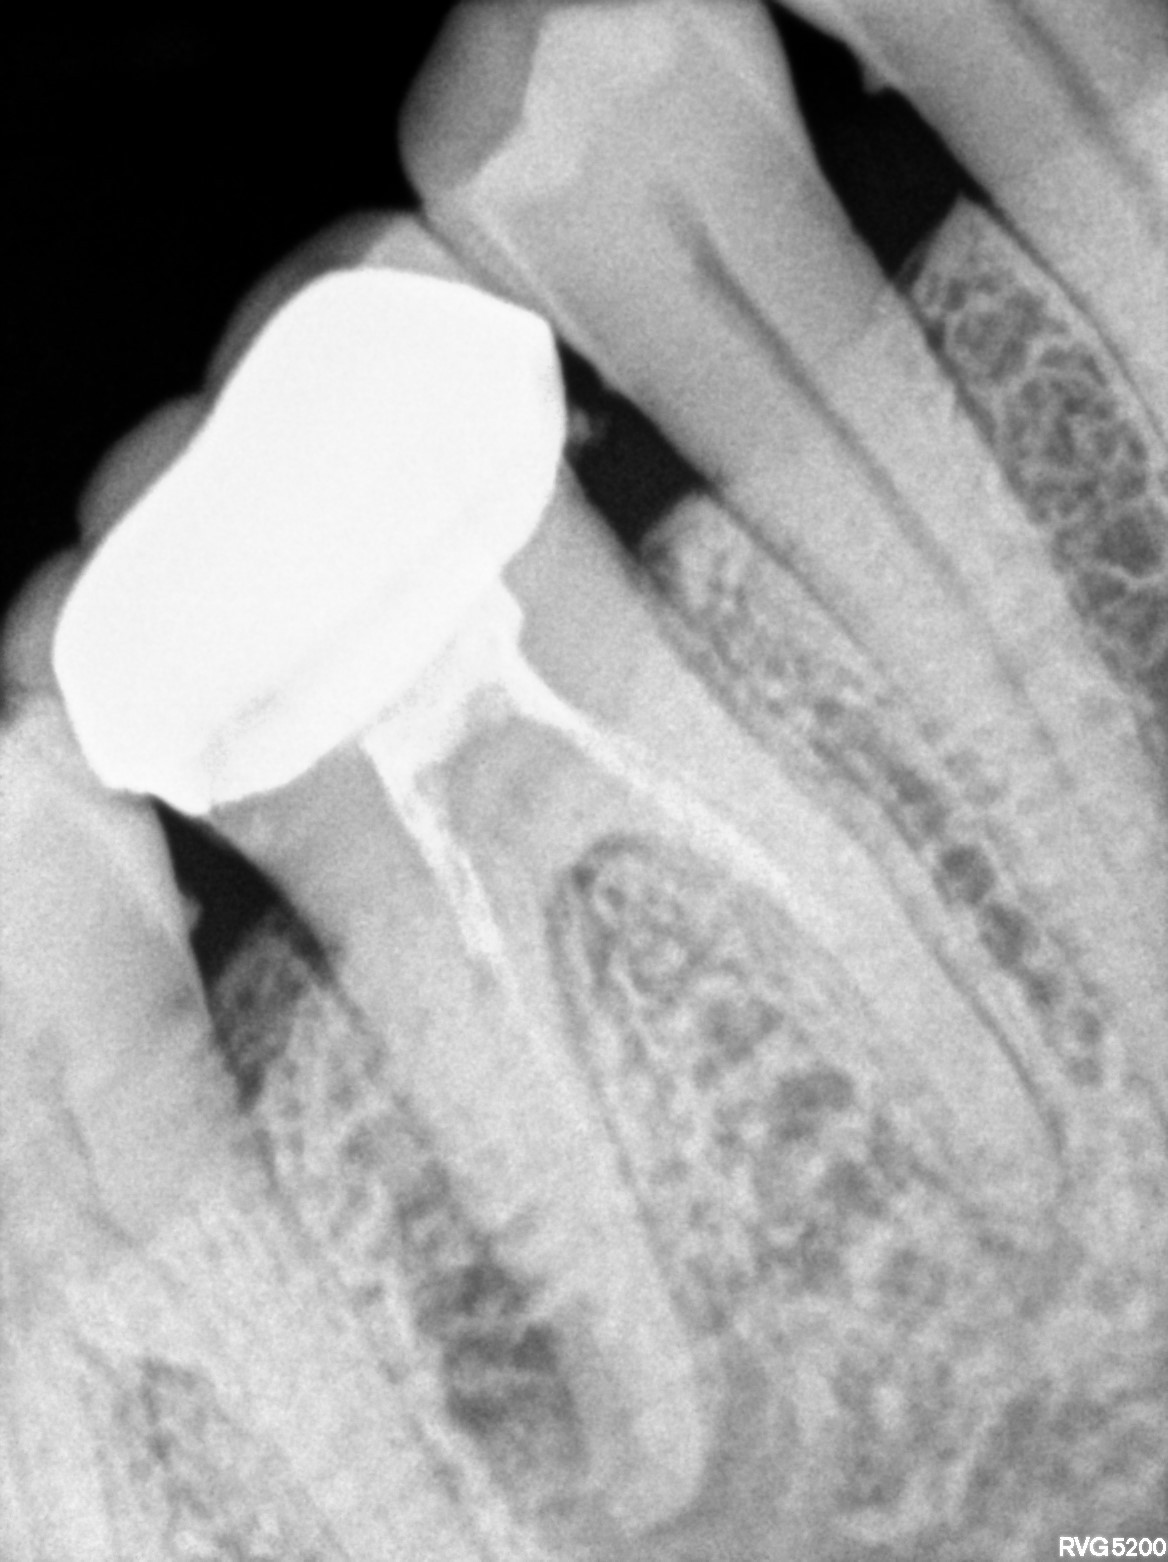

Dental Radiographs FHIR: DocumentReference · LOINC 24641-7

xray_1770481373_0.jpg

24641-7